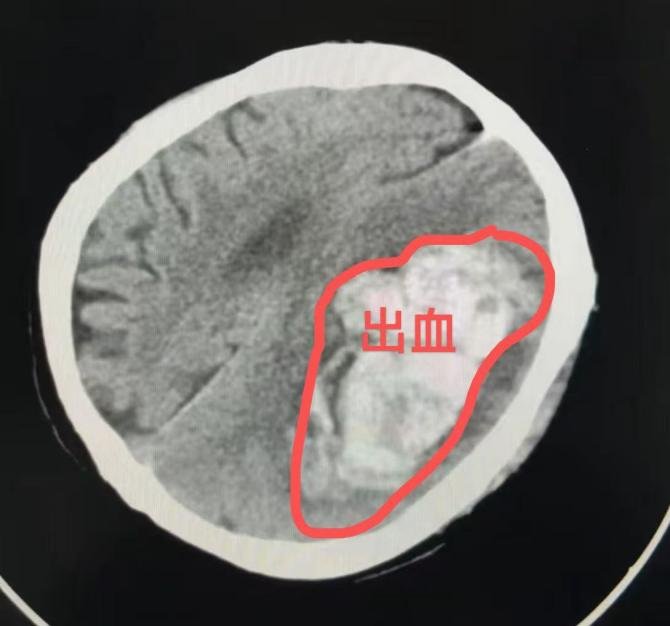

王阿婆被緊急送到北侖區人民醫院時,已處於昏迷不醒,呼之不應的狀態。頭顱CT檢查顯示顱內存在大面積出血,嚴重危及生命安全。神經外科團隊閱片後評估,出血量已達上百毫升。待急診完善頭顱CTA排除顱內血管畸形等特殊情況後,王阿婆被緊急送入手術室,在醫護團隊的默契配合下,手術順利完成,生命體徵平穩後被送入重症監護室,目前正在康復中。

出血性腦卒中